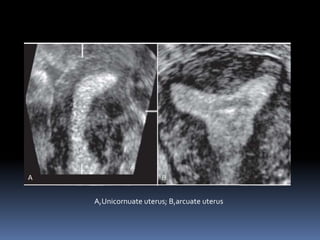

This document contains an image gallery from Dr. Mohit Goel showing various uterine anomalies and ovarian cysts. It includes images of an arcuate and unicornuate uterus, endometritis, a twisted ovarian pedicle, dermoid cysts of varying sizes and echogenicity containing hair, fat, and calcifications, and a combination dermoid cyst showing both mesh and plug structures. The gallery provides ultrasound images of different gynecological conditions for medical education and reference.